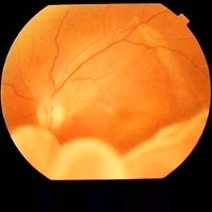

- 糖尿病视网膜病变是糖尿病的常见并发症,也是四大致盲眼病之一,其发病率和致盲率呈逐年上升趋势。的发生和进展与多种因素有关,早期诊断并积极治疗以防止或延缓其进展至关重要。对病人进行有计划、有目的的健康教育,帮助人们掌握卫生保健知识,促使人们树立

- 糖尿病视网膜病变疾病简介糖尿病视网膜病变是最常见的糖尿病慢性并发症,对视功能的损害难以逆转,是目前三大主要致盲原因之一。2016年WHO统计数据显示,中国成年人近10%患有糖尿病,总数已超1亿,随着人